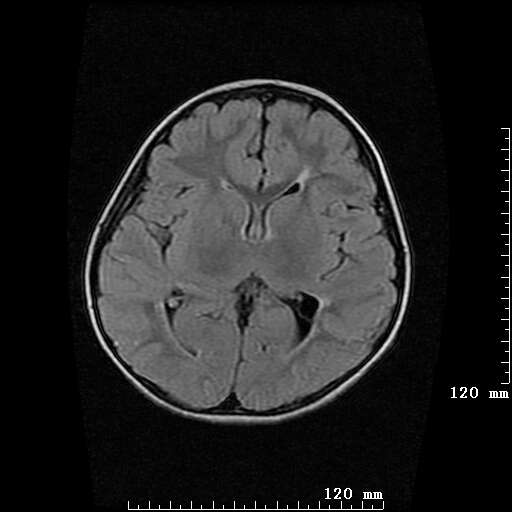

女,7岁,三岁才说话、走路。现智力尚可,走路不稳。临床怀疑大脑发育不全。

考虑 脑白质发育不良

脑折质变薄,双侧侧脑室稍扩张,支持考虑脑折质发育不良

侧脑室周围白质软化症。

考虑胼胝体发育不全,髓鞘形成不良。

支持考虑胼胝体发育不全,髓鞘形成不良。

脑裂畸形伴灰质异位

侧脑室周围白质数量减少,侧脑室不对称性扩大,左侧侧脑室后角呈方形改变,脑沟加深,结合临床考虑脑室周围白质软化症(pvl)。期待结果!

只看出灰质异位

支持脑白质发育不良。